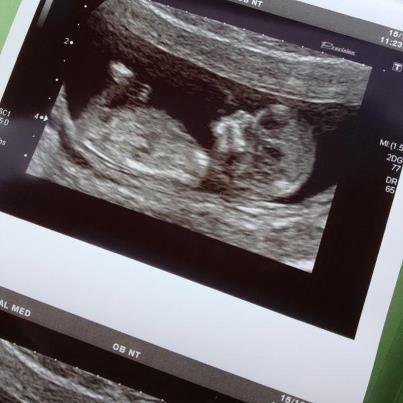

Attachment 5392 As the title says! What do you think?? Any answers thankfully received! x

maybe girl